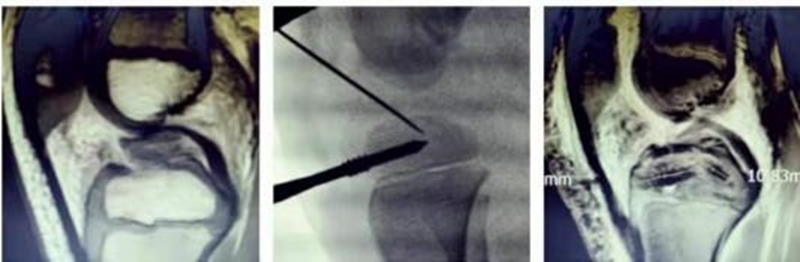

4岁男孩,游戏中跑步跌倒,扭伤左膝,迅速肿胀、疼痛。急诊DR和MRI显示前交叉韧带胫骨止点撕脱骨折,Meyers and Mckeever之III型。经镜下缝合桥技术,骨折解剖复位,固定可靠。术前MRI和术中透视,以及术后MRI如图20所示。术后3天,床旁悬吊屈膝可达90°,在伸膝支具保护下,护双拐下地平地行走,如图21所示。出院后接受运动康复及基础动作模式体能训练,并配合术后MRI复查及门诊随访。术前、术后及术后2月MRI如图22所示。

图20 术前MRI、术中透视及术后MRI